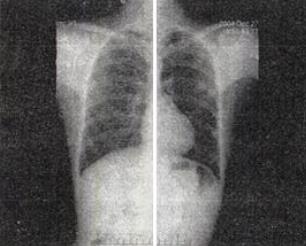

- 单项选择题 男,6岁,口唇青紫,喜蹲踞。结合X线(见图)检查,最可能的诊断是()。

D、法洛四联症

- D